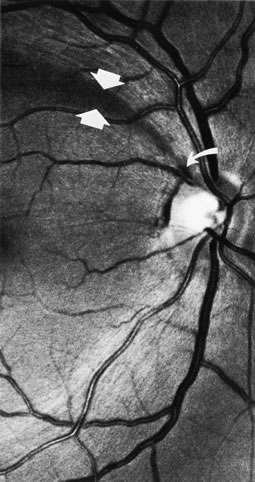

When bundles of nerve fibers drop out, their absence can be noted in the retinal sheen produced by the retinal nerve fiber layer.4,8–10,85 Such defects are easiest to see in the thickest portions of the nerve fiber layer, namely, close to the disc and especially in the arcuate bundles approaching the poles of the disc.5,6 The loss of nerve fibers can be recognized ophthalmoscopically but, as shown in Figure 41, is demonstrated most beautifully in wide-angle fundus photographs taken with blue or green filters.10,154 It is difficult to see if the background is lightly pigmented or if imperfect media produce an imperfect view of the fundus. Some observers are more skilled than others in recognizing nerve-fiber layer disease.

Fig. 41. Retinal nerve fiber layer in glaucoma. A curved wedge (between the broad arrows) represents the loss of nerve fiber bundles corresponding to a sector of the disc marked by a splinter hemorrhage (small curved arrow). (Airaksinen PJ. Mustonen E. Alanko HI: Optic disc hemorrhages precede retinal nerve fiber layer defects in ocular hypertension. Acta Ophthalmol 59:627, 1981.)